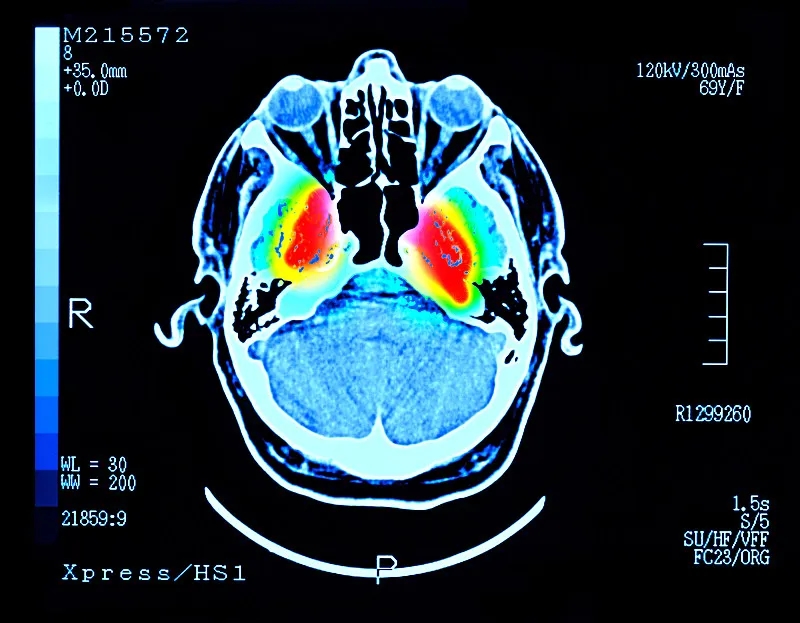

帕金森病 (PD) 是大腦中的一種疾病,它會殺死產生一種叫做“多巴胺”的化學物質的神經元。多巴胺是一種重要的化學物質,負責大腦內神經元之間的交流。細胞死亡主要發生在“黑質”,這是大腦中主要的多巴胺產生區域。

這些治療可緩解帕金森病的癥狀,但不會減緩或逆轉大腦神經細胞的損傷。隨著時間的推移,盡管進行了治療,但臨床特征會變得更糟。當患者被診斷出患有帕金森癥時,他們通常已經患病多年,并且黑質內的多巴胺細胞已經丟失了一半以上。早期檢測帕金森癥的測試可能有所幫助,但科學家們正在尋找一種方法來替換受損的細胞。